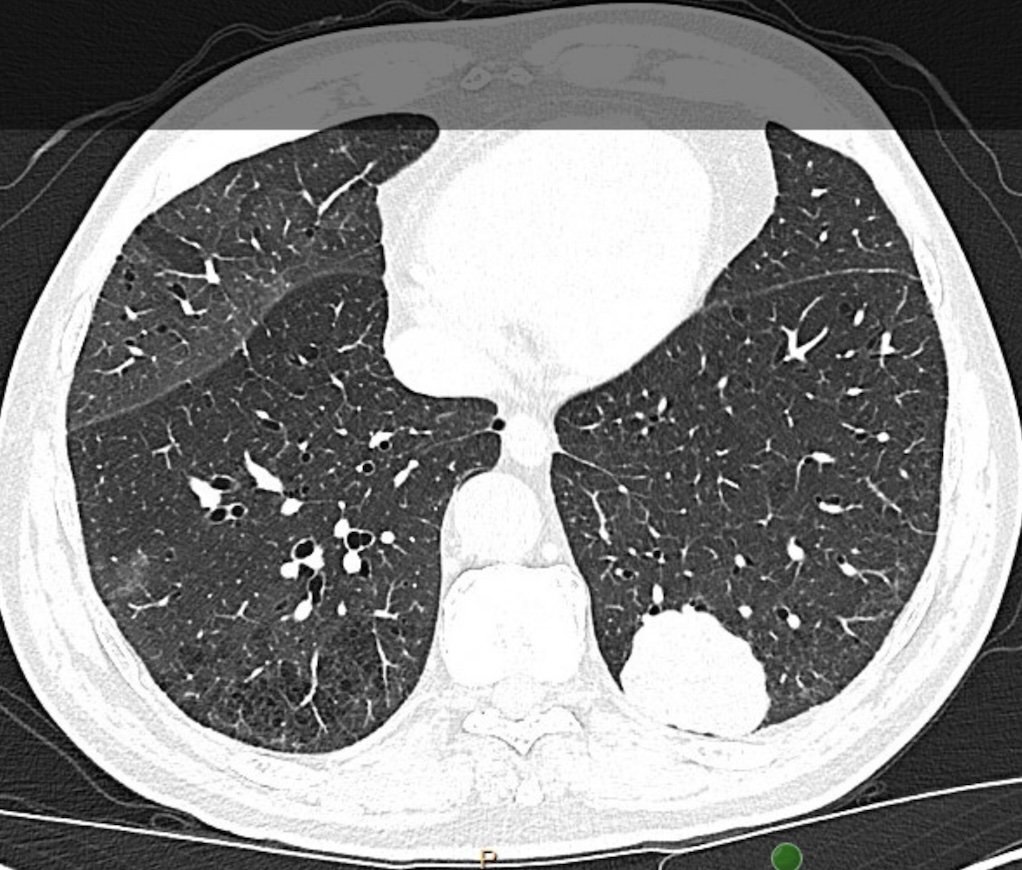

INSIDE LOOK 👀 Read from the upcoming issue (December 9): A CHEST research letter compares the currently described methods of identifying CT scan lesion location within the lung.

Read more in the journal CHEST®: hubs.la/Q03VjqGG0

#MedEd #JournalCHEST #LungCancer